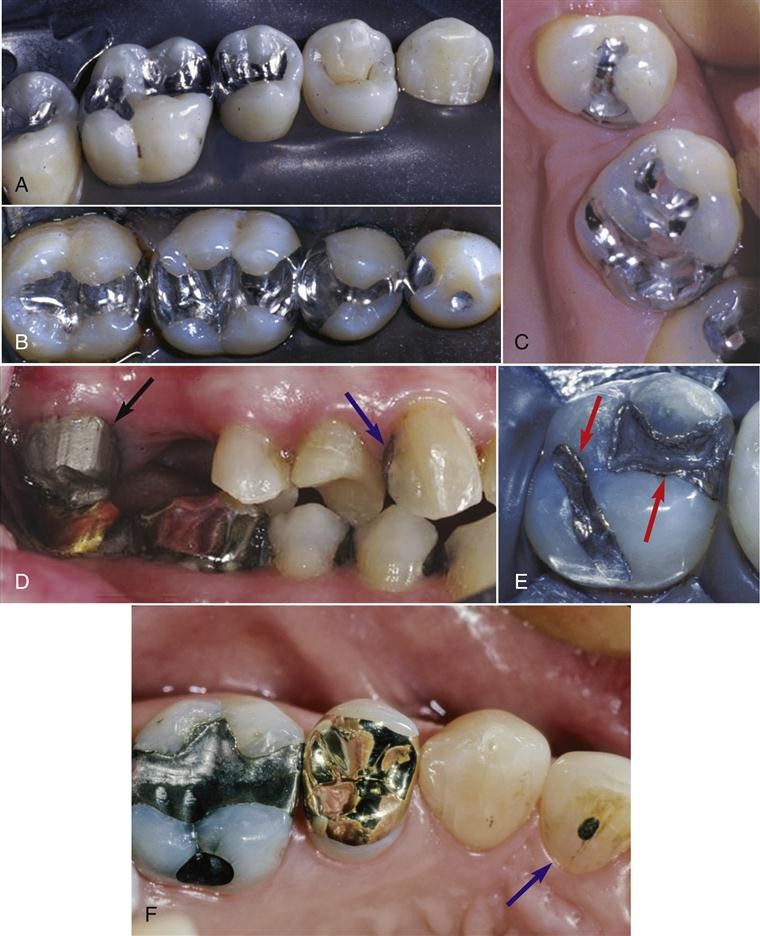

(1)金属嵌体:有贵金属及非贵金属合金嵌体。金合金化学性能稳定,有良好的延展性能和机械性能,是制作后牙嵌体理想的传统修复材料(彩图3—10)。

(2)树脂嵌体:采用高强度复合树脂材料在模型上加工成形或CAD/CAM成形,调磨抛光后用树脂粘接材料粘接于牙体组织上。树脂嵌体为牙色修复体,易修补,对对拾牙磨耗小,美观性好。

(3)瓷嵌体:采用陶瓷材料在模型上加工成形或CAD/CAM成形,用树脂粘接材料粘接于牙体组织上。不同陶瓷材料有不同的加工工艺,如直接在耐火材料代型上制作的烤瓷嵌体;CAD/CAM磨削出的瓷嵌体;在模型上做熔模包埋后热压铸成形的铸瓷嵌体;采用金沉积法制作组织面衬底后做的烤瓷嵌体。瓷嵌体具有优良的美学性能。